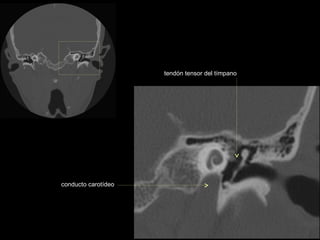

CATEDRA DE RADIOLOGIA U.N.L.P.   Hueso temporal normal              Edición 2002

seno maxilar

conducto

carotídeo

auditivo externo

protuberancia

occipital externa

trompa de Eustaquio

conducto auditivo externo

celdillas mastoideas

eminencia piramidal

seno timpánico

receso del n. facial

nervio facial (3era)

estribo (cruras)

nervio facial

ventana oval

martillo

yunque

cóclea

vestíbulo

conducto semicircular externo

articulación yunque/martillo

conducto auditivo interno

conducto semicircular posterior

antro mastoideo

celdillas retrolaberínticas

conducto semicircular

superior

conducto semicircular superior

cabeza del martillo

procidencia de meninges

tendón tensor del tímpano

conducto carotídeo

espina supra y retrotimpánica

nervio facial (2da)

nervio facial (1era)

cresta falciforme

promontorio

estribo

membrana

timpánica

externo

ventana redonda